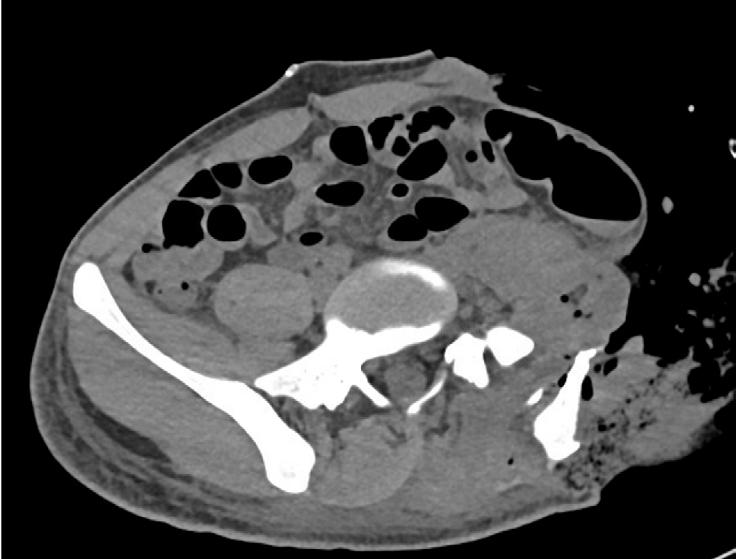

PREOPERATIVE IMAGING

E) CT Abdomen, Pelvis Axial F) Sagital G) Coronal